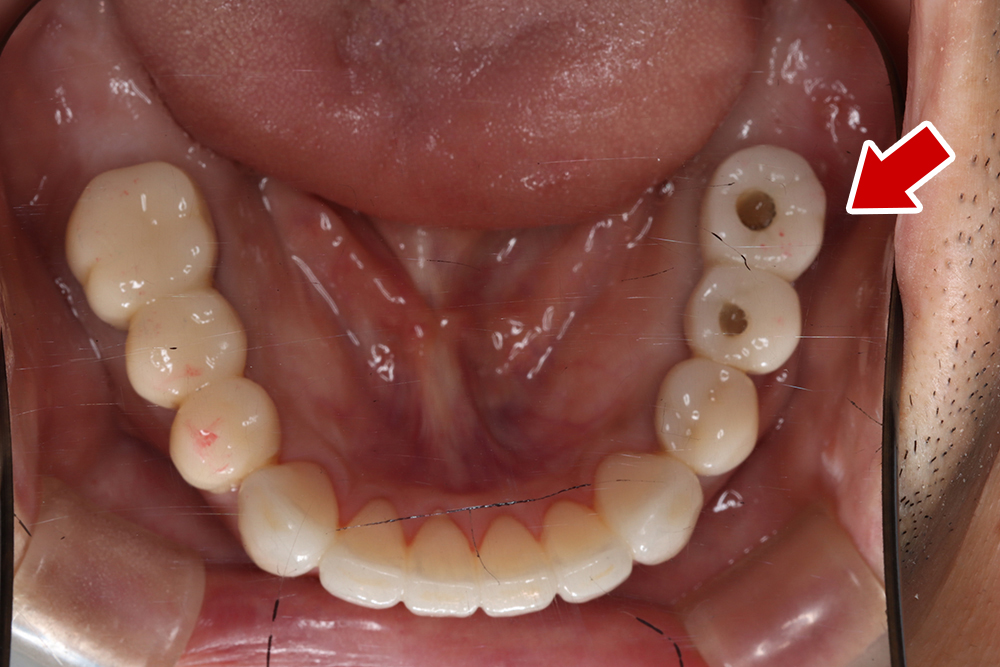

53歳 男性

- 主訴

- 全然噛めない。上の歯が取れてきた

- 処置内容

- 上顎:8本 下顎:2本

- 治療費用

- 上顎:約320万円(税込)、下顎:約160万円(税込)

- 治療期間

-

上顎:1年(仮歯まで8か月)

下顎:8か月(仮歯まで5か月)

- リスク

- 上部構造物、仮歯の破折、術後の腫れ(3日)、人工歯根脱落リスクがあります